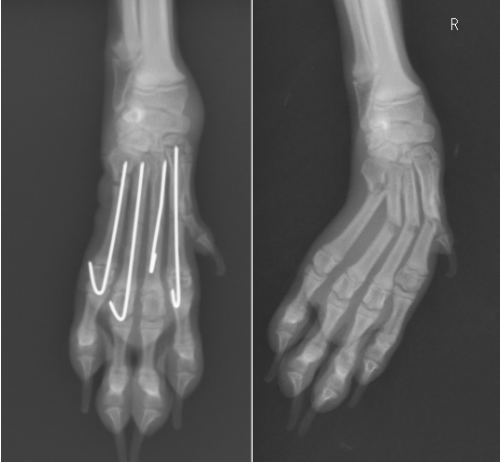

ねこちゃんの前腕手根関節脱臼 京都府 宇治市 いちのさか動物病院 長谷川先生とちーすけのブログ

中野区 練馬区 江古田の森ペットクリニックの症例紹介 一般外科症例をご紹介しております

治療例 骨折 猫 なかがわアニマルクリニック 手稲区と西区の境の動物病院